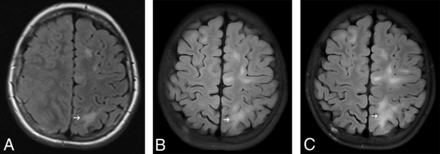

In our cohort, 10 of 14 patients (71%) had single or multiple nonspecific patchy subcortical white matter T2-FLAIR hyperintensities, most commonly in the frontal and parietal lobes, but occasionally in the cerebellum and/or the brain stem (Table 2). No mass effect, enhancement, or restricted diffusion were noted in these lesions (Figs 1 to 3). Most of the lesions were stable or showed very modest changes during the surveillance period (Fig 4). In 3 patients, a gradual transformation toward overt brain tumors was observed on surveillance studies (2 with glioblastomas and 1 with diffuse astrocytoma; Figs 2 and 3, respectively). Occasionally, additional new lesions emerged during the follow-up period, too.

Surveillance brain MR imaging studies of a boy with CMMRD (patient 2). Serial T2-FLAIR imaging shows nonspecific subcortical hyperintensities (arrows) slowly increasing in size (10 years of age, A; 15 years of age, B). At 18 years of age (C), there is an infiltrative lesion involving the right insula (asterisk) and base of the right frontal lobe. Biopsy results indicated diffuse astrocytoma (WHO II). Three months later (D), marked increase in the left frontotemporal lesion was obvious along with central necrosis (arrowhead). This lesion was resected, and pathologic testing indicated glioblastoma.

MR images of a girl with CMMRD (patient 6) and glioblastoma (not shown). A gradual increase in frontoparietal subcortical T2-FLAIR hyperintensities (arrows) is noted during 2 years of surveillance (7 years of age, A; 8 years of age, B; and 9 years of age, C).